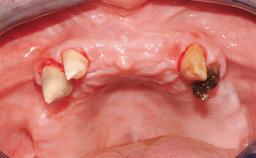

The staged approach permits the transition from an “irrational to treat”dentition to a full arch implant supported restoration without any need to use a removable provisional prosthesis or to apply the immediate-placement and immediate-loading techniques. A failing dentition is the usual indication for a staged treatment. On the other hand, the dentition should still contain many residual teeth, but with few or none of them being suitable for use as definitive abutments for a full-arch fixed restoration.This situation is usually the result of advanced periodontal disease or of the failure of an extensive fixed prosthesis.